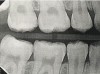

Interproximal insertion of SDF is demonstrated in different patients in Figure 3 through Figure 11. Various diameters and brands of soft dental picks may be used depending on the closeness of the proximal surfaces and ease of insertion; for example, some picks are designed for use in wider spaces between teeth. This protocol also offers versatility. Figure 3, for example, shows the simultaneous use of three thin soft dental picks to saturate proximal surfaces with SDF in a teenaged patient; the treated regions were subsequently covered with fluoride varnish (Figure 4). This patient was initially treated in April 2019 (Figure 5), with an identical re-application 3 months later. As shown in Figure 6, the December 2019 bitewing film revealed good results with the possible exception of the contact regions of the maxillary first and second molars. New SDF application was completed in the December appointment.

Fig 3. Three thin soft dental picks were used simultaneously for SDF proximal surface saturations in a teenaged patient (Fig 3). After 60 seconds, the treated regions were covered with 5% fluoride varnish (Fig 4). A comparison can be seen of pre-SDF-treatment bitewing films (Fig 5) and 8-month post-SDF bitewing films (Fig 6) for the patient shown in Fig 3 and Fig 4. Radiolucencies were similar or improved, except for contact of maxillary first and second molars.

Fig 6. Three thin soft dental picks were used simultaneously for SDF proximal surface saturations in a teenaged patient (Fig 3). After 60 seconds, the treated regions were covered with 5% fluoride varnish (Fig 4). A comparison can be seen of pre-SDF-treatment bitewing films (Fig 5) and 8-month post-SDF bitewing films (Fig 6) for the patient shown in Fig 3 and Fig 4. Radiolucencies were similar or improved, except for contact of maxillary first and second molars.

Figure 6